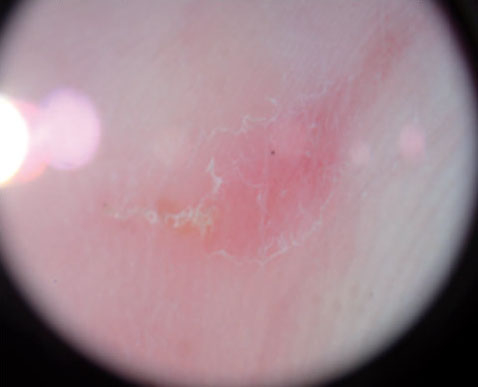

Piqures Et Boutons De Punaises De Lit Comment Les Reconnaitre